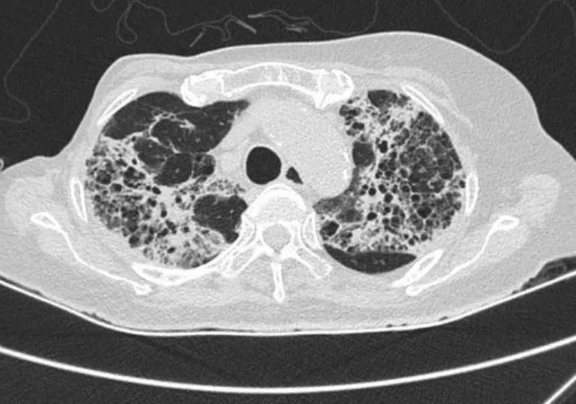

*患者影像檢查

66歲的徐阿姨因"反復(fù)高熱伴呼吸困難"轉(zhuǎn)入我院。該患者既往有乳腺癌手術(shù)史,此次發(fā)病已輾轉(zhuǎn)多家三甲醫(yī)院,診斷為"重癥肺炎、I型呼吸衰竭",曾出現(xiàn)消化道出血等嚴(yán)重并發(fā)癥。轉(zhuǎn)入時(shí)持續(xù)呼吸機(jī)輔助通氣,存在嚴(yán)重感染性休克、多器官功能衰竭,病情極其危殆。